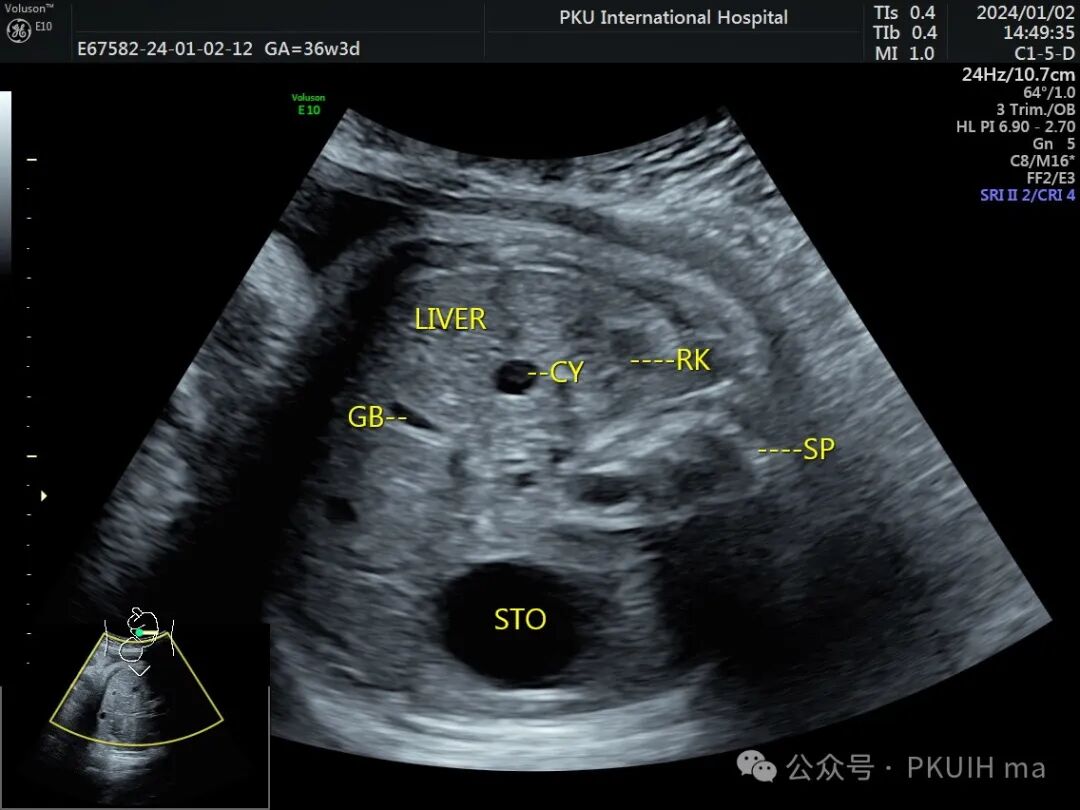

上图是一例晚孕期发现肝内囊性占位,多次复查考虑为单纯肝囊肿。肝囊肿一般位于肝实质内,右叶多见,需要和胆总管囊肿鉴别,胆总管囊肿多靠近胆囊,且周边可见胆管回声,呈毛刺样或鼠尾样,肝囊肿壁多完整光滑。